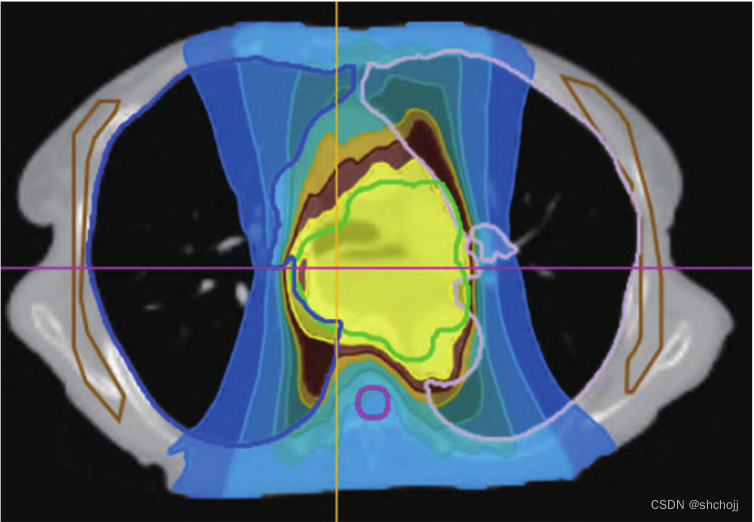

Dose Color Wash:利用色阶进行直观的绝对剂量的评估

剂量分布:二维/三维等剂量线进行评估

剂量冷点:靶区内低于处方剂量体素集合,通常用DVH进行评估,最低剂量的体积如DVH99%体积,相对应的剂量需要≥95%处方剂量。冷点位置与范围和肿瘤控制率密切相关。

剂量热点:剂量>115%处方剂量的体素集合,靶区内≤115%处方剂量,理想计划一般要求≤110%。热点位置与范围和放疗损伤密切相关

三维剂量分布:不同轴面逐层分析;

高计量点位置

审计各靶区是否按照预设剂量分布覆盖,并达到预期目标

PTV内未达到的处方剂量位置

正常组织所受剂量的范围及空间分布

等剂量线分布特征

5、冷热点(cold&hot)

冷点:PTV内不应该有。

热点:PTV外不应该有。

冷热点空间分布

- GTV内高剂量点可接受